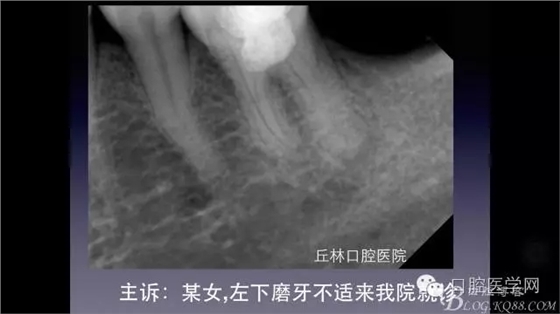

一例36根管再治療,五個(gè)根管冷側(cè)加壓病例